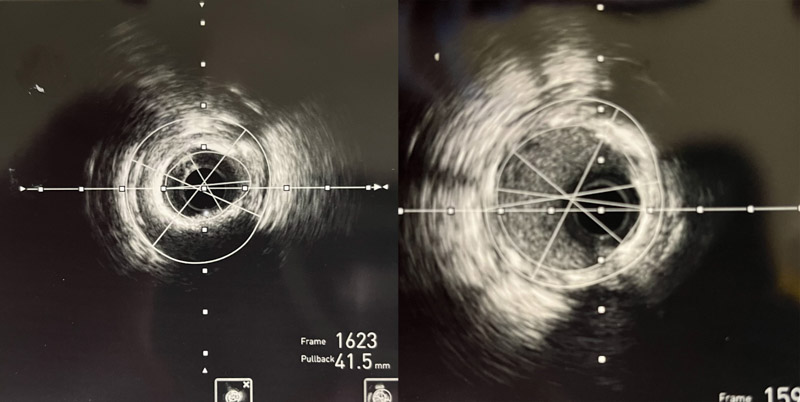

術(shù)中,心血管內(nèi)科介入團(tuán)隊將Shockwave C2 IVL 3.0*12mm 震波球囊置入前降支病變處,以4-6atm進(jìn)行擴(kuò)張后觸發(fā)8次10秒沖擊波,實施鈣化斑塊碎裂術(shù),術(shù)后支架膨脹不全處明顯擴(kuò)張,并順利于前降支近中段植入1枚支架。復(fù)查IVUS可見鈣化斑塊碎裂,支架貼壁和膨脹良好,血管擴(kuò)張成形滿意,術(shù)后患者胸痛癥狀明顯好轉(zhuǎn)。

▲震波前、后IVUS對比圖像